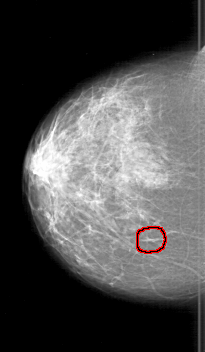

D_4197_1.RIGHT_CC

RIGHT_CC LINES 5971 PIXELS_PER_LINE 3481 BITS_PER_PIXEL 12 RESOLUTION 43.5 OVERLAY

FILE: D_4197_1.RIGHT_CC.OVERLAY

TOTAL_ABNORMALITIES 1

ABNORMALITY 1

LESION_TYPE CALCIFICATION TYPE PUNCTATE DISTRIBUTION CLUSTERED

ASSESSMENT 0

SUBTLETY 2

PATHOLOGY BENIGN

TOTAL_OUTLINES 1

BOUNDARY